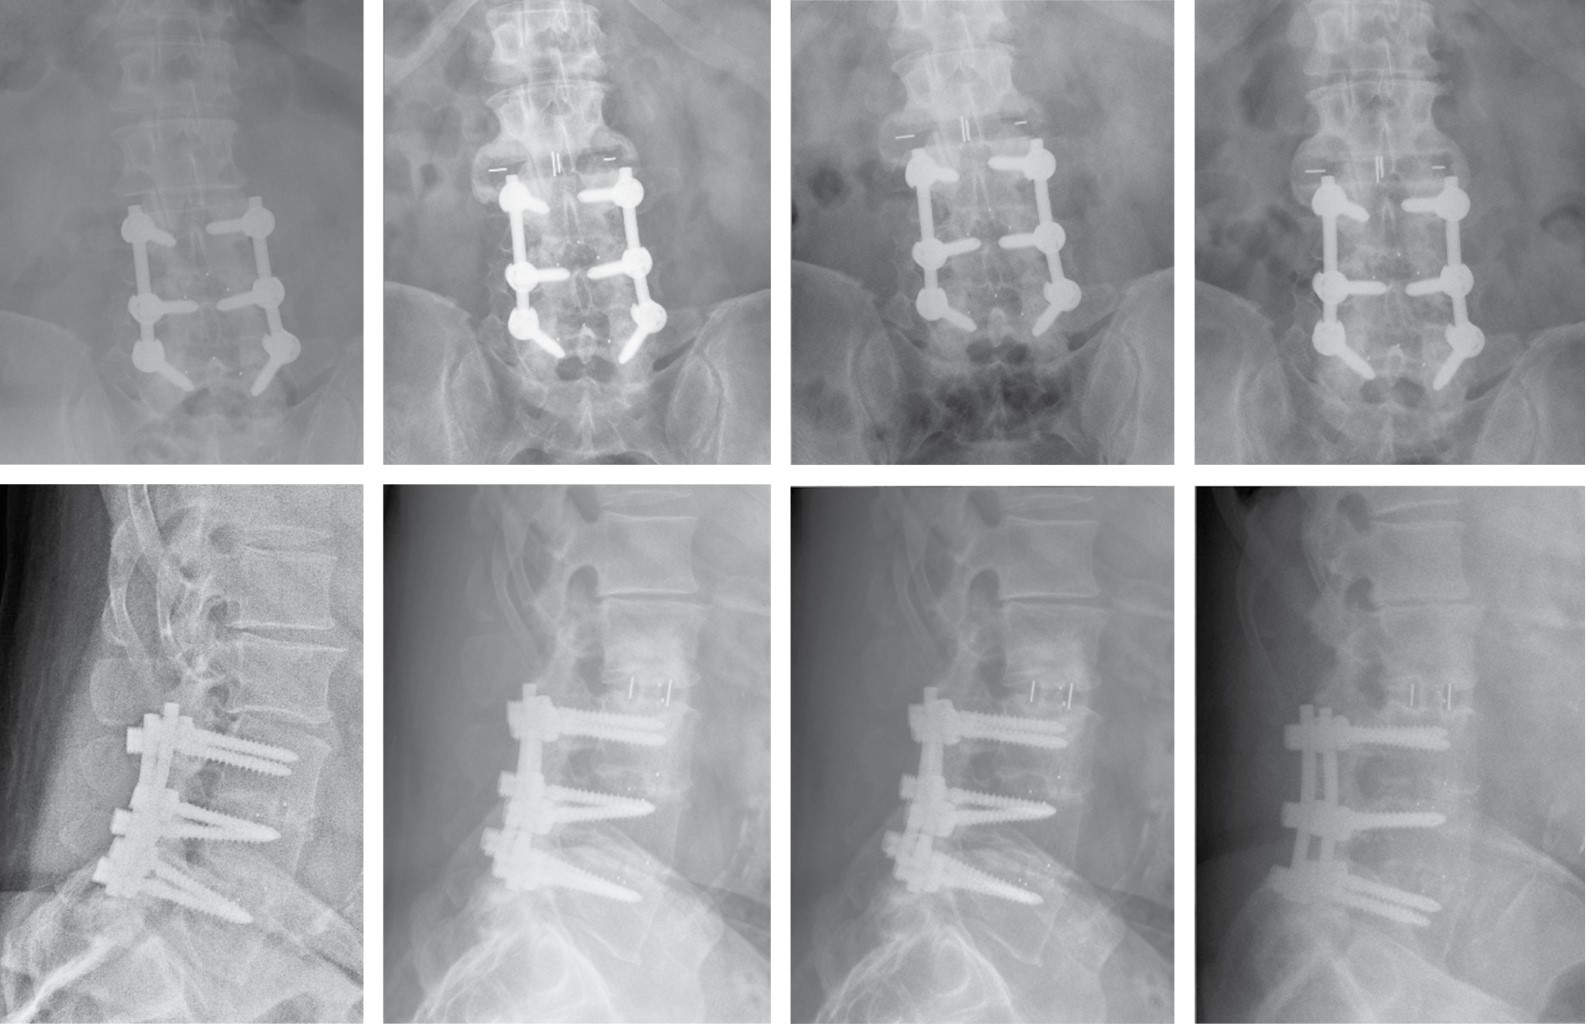

Con respecto a la tasa de fusión, con el TC lumbar al año de la cirugía se encontraron puentes óseos con fusión completa en 16 pacientes (55.2%), con fusión incompleta en ocho pacientes (27.6%) y falta de fusión en cinco pacientes (17.25%) de la serie, sin evidencias significativas entre los grupos (Figura 3). Considerando la tasa de fusión global (total y parcial) analizada mediante TC es de 84.3%24 y distinguiendo los grupos de estudio: 88% Ti y 82% PEEK (p = 0.53) (Tabla 4).

Figura 3